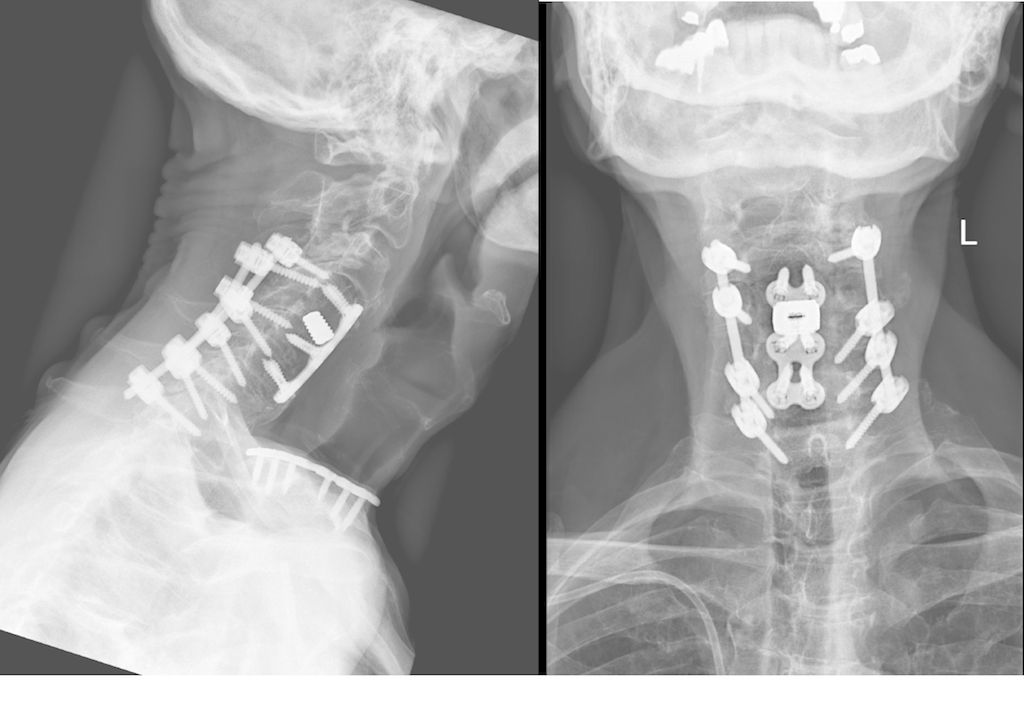

Fallbeispiel 1

Beispiel für die Implantation zervikaler Pedikelschrauben. In diesem Fall kam es bei einem 61-jährigen Patienten 10 Jahre nach anteriorer zervikaler Diskektomie und Fusion (ACDF) C4/5 und ventraler Verplattung C4–6 zu einer Ankylosierung auch von C6/7. Nach Sturz kam es zu einer Fraktur bei C6/7 mit begleitender Bogenfraktur und auch Beteiligung der dorsalen Ligamenta (Abb. 1 und 2). Klinisch bestanden ausgeprägte Nackenschmerzen und kein neurologisches Defizit. Es wurde die Indikation der dorsalen Verschraubung von C4 auf Th1 gestellt. Intraoperativ wurde routinemäßig zusätzlich eine kleine Referenzschraube in einer Lamina – entfernt von der Dornfortsatz-Referenzklemme für die Navigation – gesetzt. Mit dieser konnte intraoperativ die Genauigkeit der Navigation exakt überprüft werden (Abb. 4 und 5). Mittels navigierter High-Speed-Fräse wurden die Schraubenkanäle vorgebohrt (Abb. 6), im Anschluss wurde der Bohrkanal ausgetastet und die Schrauben wurden implantiert. Abbildung 7 zeigt eine Röntgenkontrolle 3 Monate postoperativ.